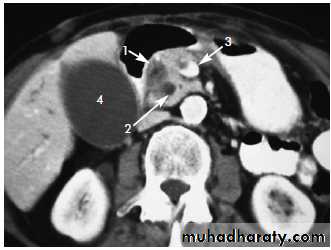

• MRI, CT scan: will show the outline and the area of damage. Calcifications seen on CT but not on MRI.

CT scan Ca pancreas• (b) Carcinoma of the body and tail:

• CT scan: the preferred test is contrast enhanced CT scan:• It guides for percutaneous FNAC. If the tumor is small (less than 4 cm) and confined to the head without evidence of distant metastasis or vascular invasion should undergo surgery.